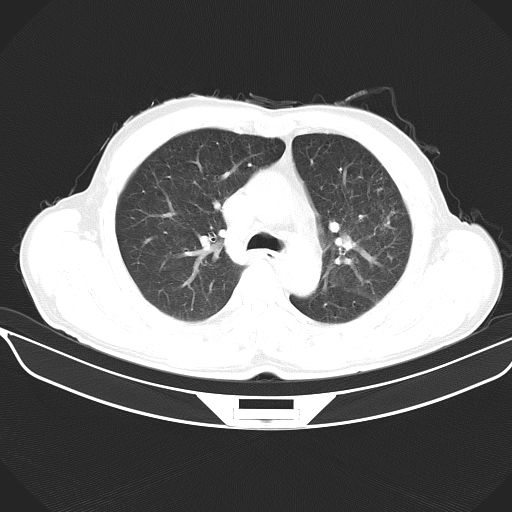

以下是引用心路寻觅在2010-3-1 10:23:00的发言:[br]1、考虑左肺上叶周围型肺癌[br]2、右上肺陈旧性病灶。[br][br][本贴已被 心路寻觅 于 2010-3-1 10:40:18 修改过]

以下是引用shuiyuan在2010-3-1 10:45:00的发言:[br]考虑左肺上叶中心型肺癌伴阻塞型炎症,邻近胸膜受侵。